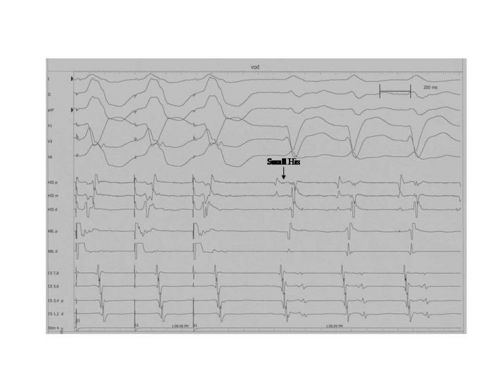

Pseudo V-A-A-V response

A pseudo VAAV response can occur when performing the Ventricular Overdrive Maneuver in patients with a long HV interval.(See Figure Below) This is why is important to include the His deflection in your tracings. In the figure below, the Ventricular Overdrive Maneuver resulted in a VAAHV response. This response can be seen in

- AVNRT and AVRT when the baseline HV interval is prolonged (as in this case) or

- When VOD pacing results in a VA on the slow pathway and the first A after termination of ventricular pacing is from the second to last ventricular paced beat.